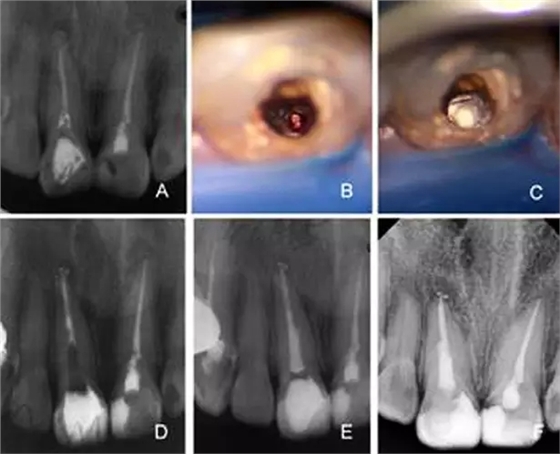

A:術(shù)前X線根尖片 B:術(shù)前CBCT定位折斷器械位置 C:顯微鏡下尋找折斷器械 D:顯微鏡下隱裂紋清晰可見 E:術(shù)后X線根尖片 F:一年后復(fù)查X線根尖片

A:根管唇側(cè)穿孔,牙膠尖于穿孔處超填,根尖及近中側(cè)方有骨密度減低

影像 B:根管顯微鏡輔助下取出牙膠尖 C:MTA修補(bǔ)側(cè)穿孔 D:根管部分

充填 E:2月后根管及冠方充填 F:8個(gè)月后復(fù)查X線片可見暗影區(qū)減小